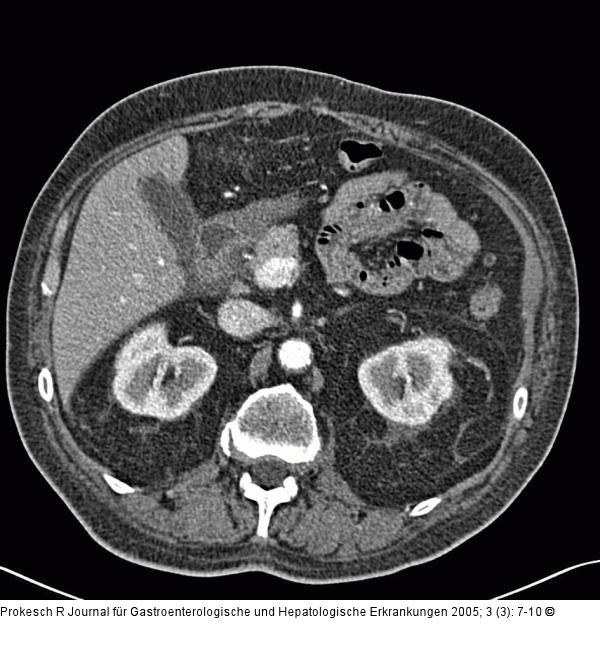

Abbildung 3a-b: Groove-Pankreatitis Pankreatitis, Computertomographie: Mäßiges Ödem zwischen Pankreaskopf und Duodenum (a) sowie im mesenteriellen Fettgewebe (b): Sogenannte Groove-Pankreatitis. |

Pankreatitis, Computertomographie: Mäßiges Ödem zwischen Pankreaskopf und Duodenum (a) sowie im mesenteriellen Fettgewebe (b): Sogenannte Groove-Pankreatitis. |